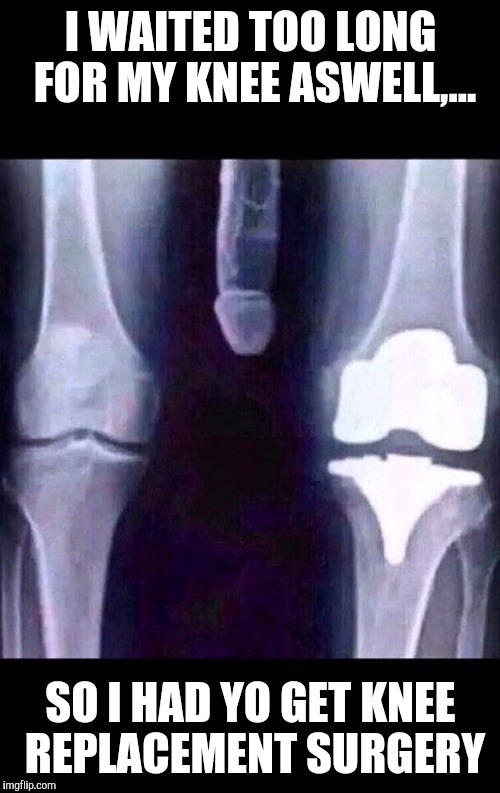

25+ Best Knee Surgery Memes t… r/Shark_Park Hair Tie And Knee Pads Meme Find the gifs, clips, and stickers that make your conversations more positive, more. With tenor, maker of gif keyboard, add popular knee pads animated gifs to your conversations. With tenor, maker of gif keyboard, add popular hair tie animated gifs to your conversations. Make your own images with our meme generator or animated gif maker. Images tagged kamala knee pads.. Hair Tie And Knee Pads Meme.